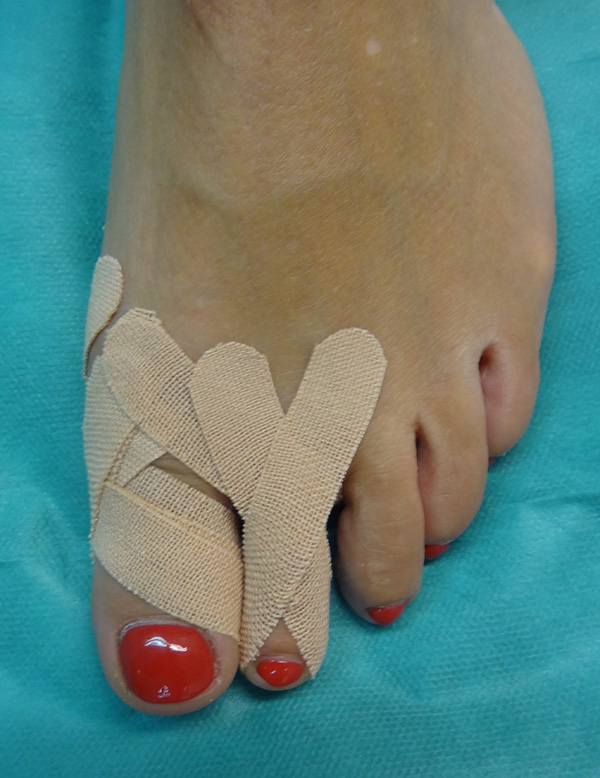

Sämtliche Operationsschritte werden über kleine Stichinzisionen durch die Haut durchgeführt. Isham beschrieb das Verfahren ohne Osteosynthese. Da es sich bei den knöchernen Korrekturen um mediale Closing wedge Osteotomien handelt, werden diese anschließend durch spezielle Zügelverbände (Tape) in Position gehalten. Postoperativ ist eine sofortige Vollbelastung im flachen Verbandsschuh möglich, der Wechsel auf Konfektionsschuhe erfolgt meist nach 4 bis 5 Wochen.

• Notwendigkeit der Anlage von Spezialtapes. Diese sollte nur vom Operateur selbst gewechselt werden, wöchentliche Kontrollen mit Tapewechsel notwendig.

• Verbandmaterial zum Anlegen eines Redressionsverbandes (sterile Kompressen, sterile Watte, Haftbinde, Tape).

Postoperative Behandlung

• Verbandswechsel (vom Operateur selbst) 7, 14, 21 und 28 Tage postoperativ mit Freigabe nach 4-6 Wochen.

• Korrekturverlust durch falsche Tape-Technik postoperativ.